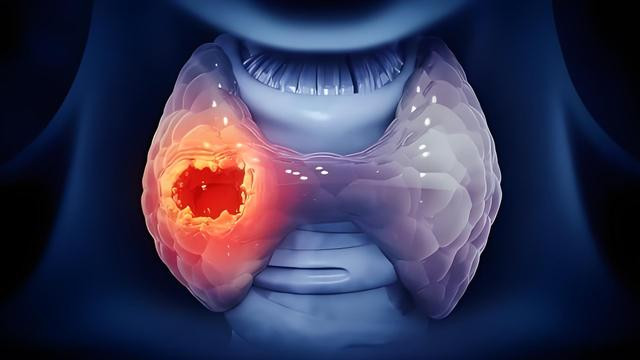

“结节癌变”不是吓唬人,但也别被吓坏了

有人一听“结节癌变”,脸都白了。其实根据研究,甲状腺结节癌变的比例不到5%,而这5%中,大部分是甲状腺乳头状癌,是一种极易治疗、预后良好的癌症。